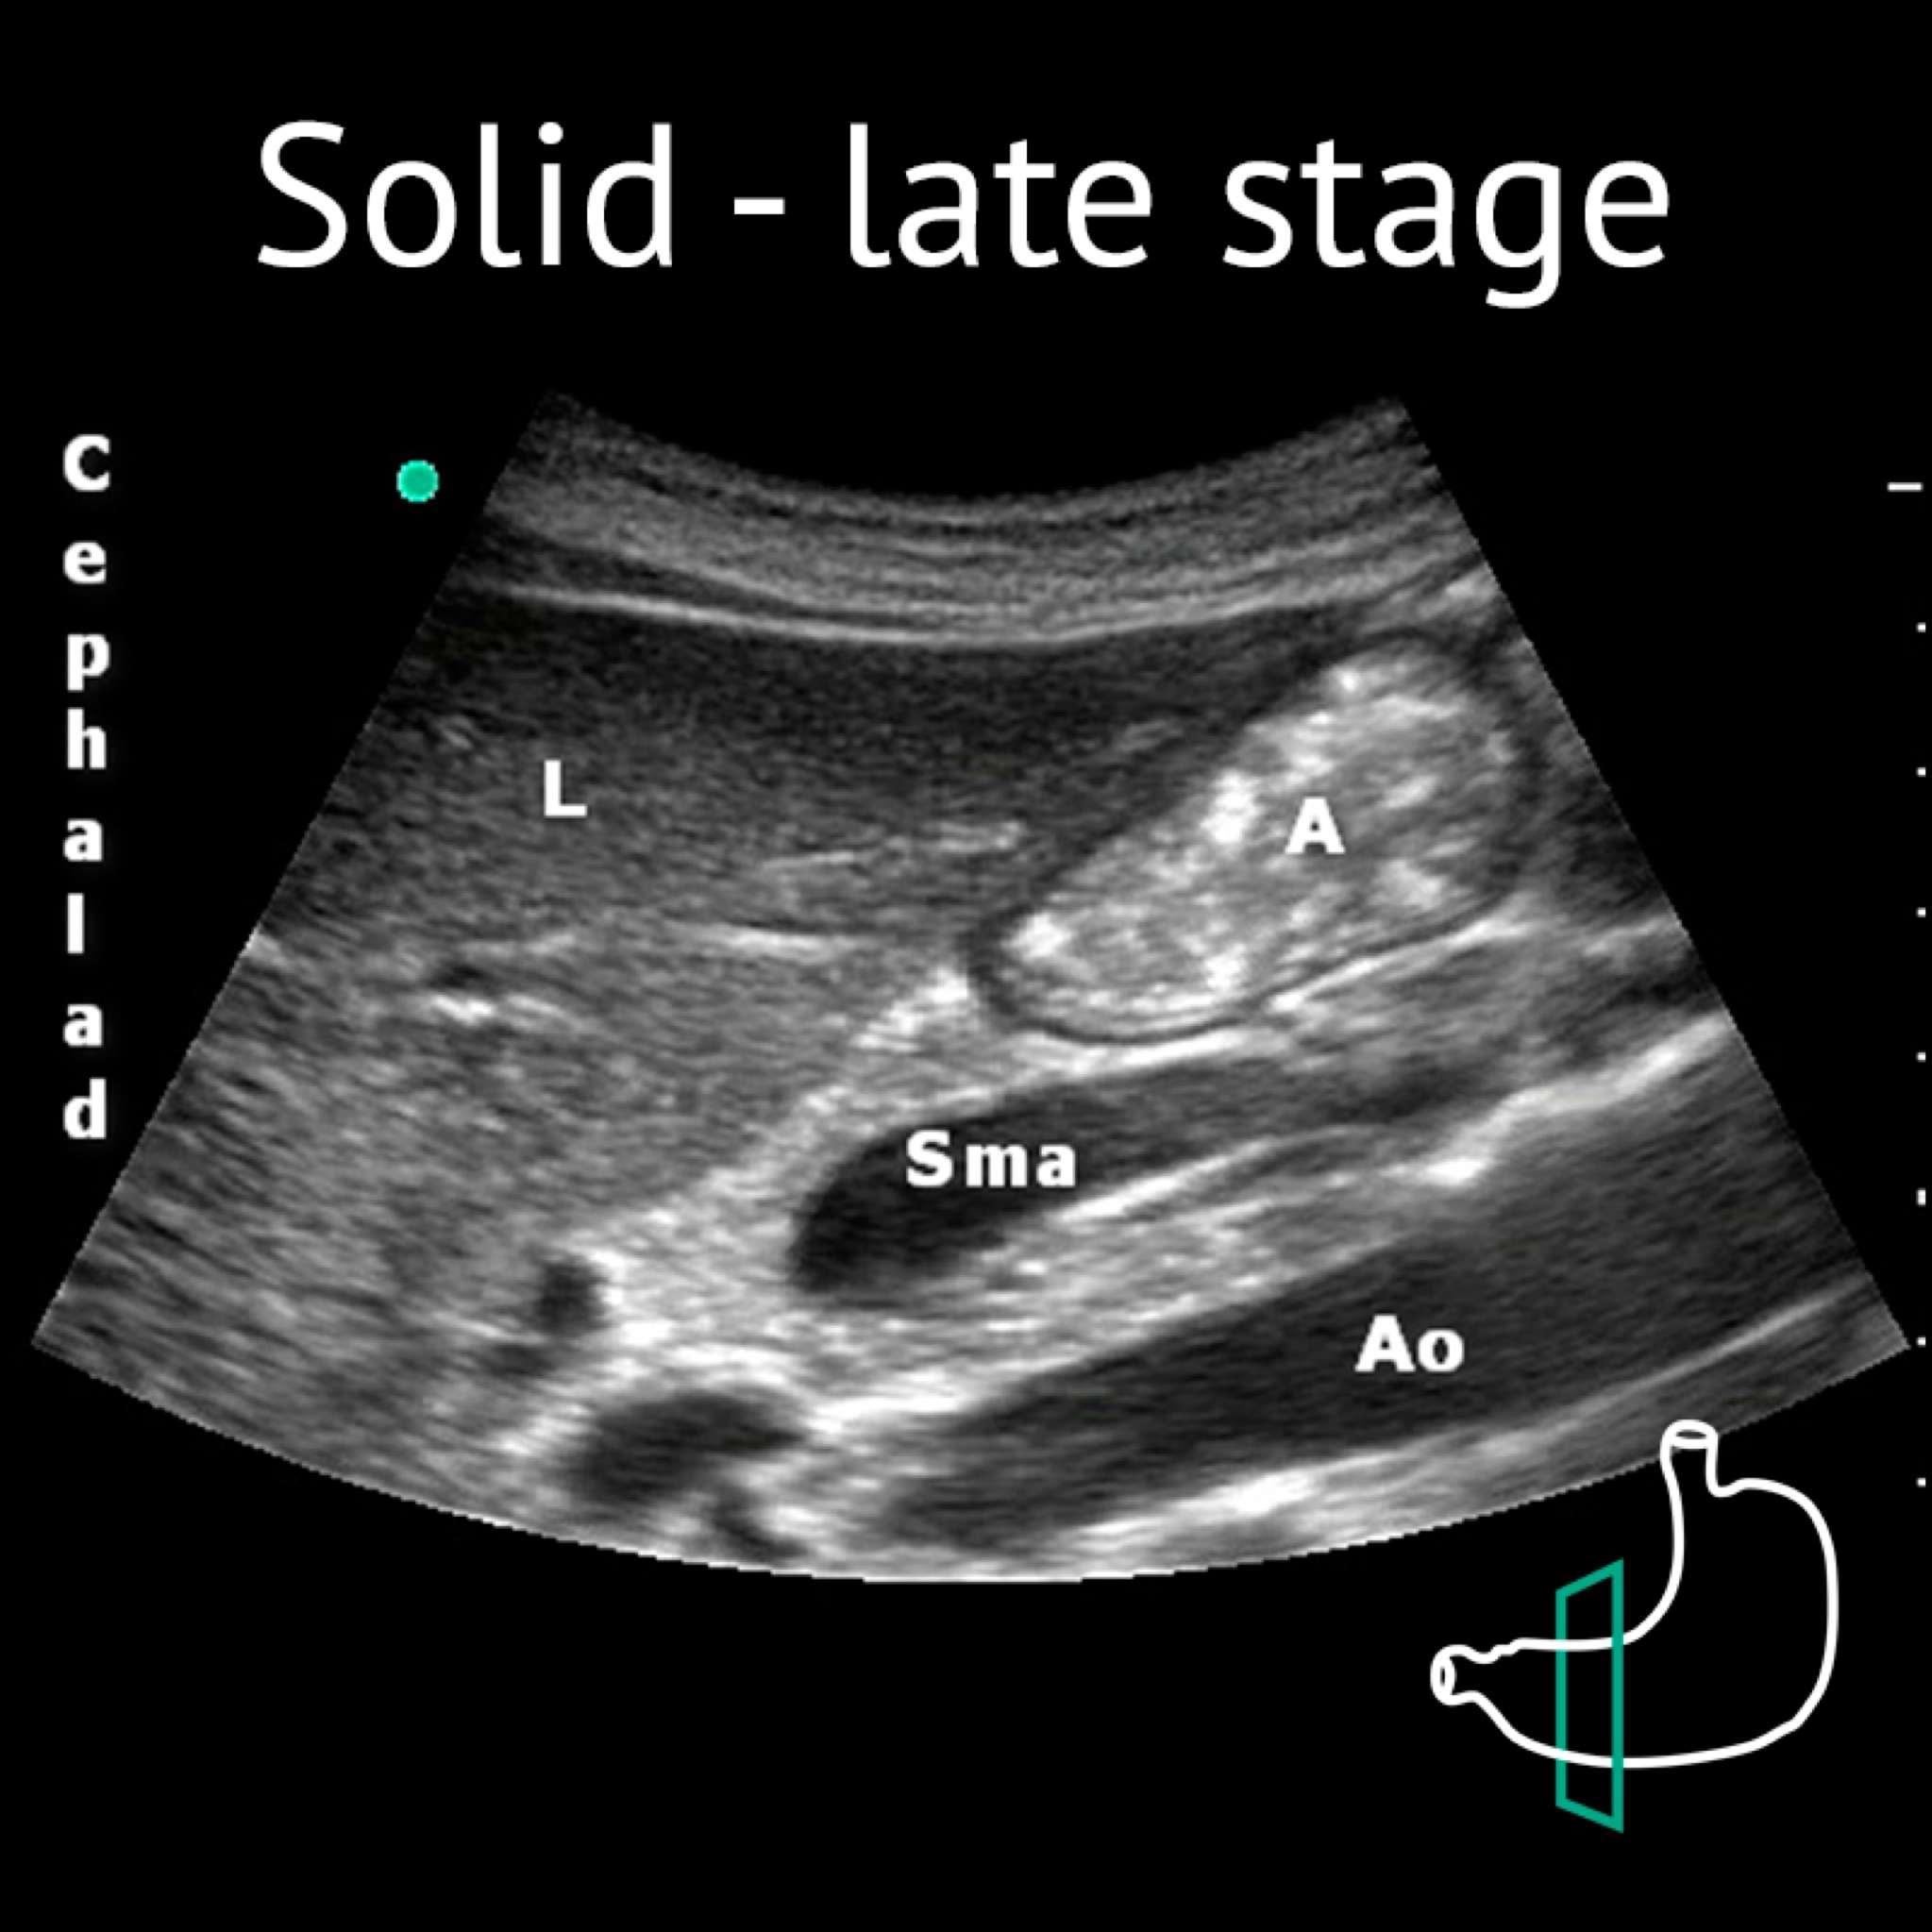

A: antrum; Ao: aorta; L: liver; P: pancreas; Sma: superior mesenteric artery